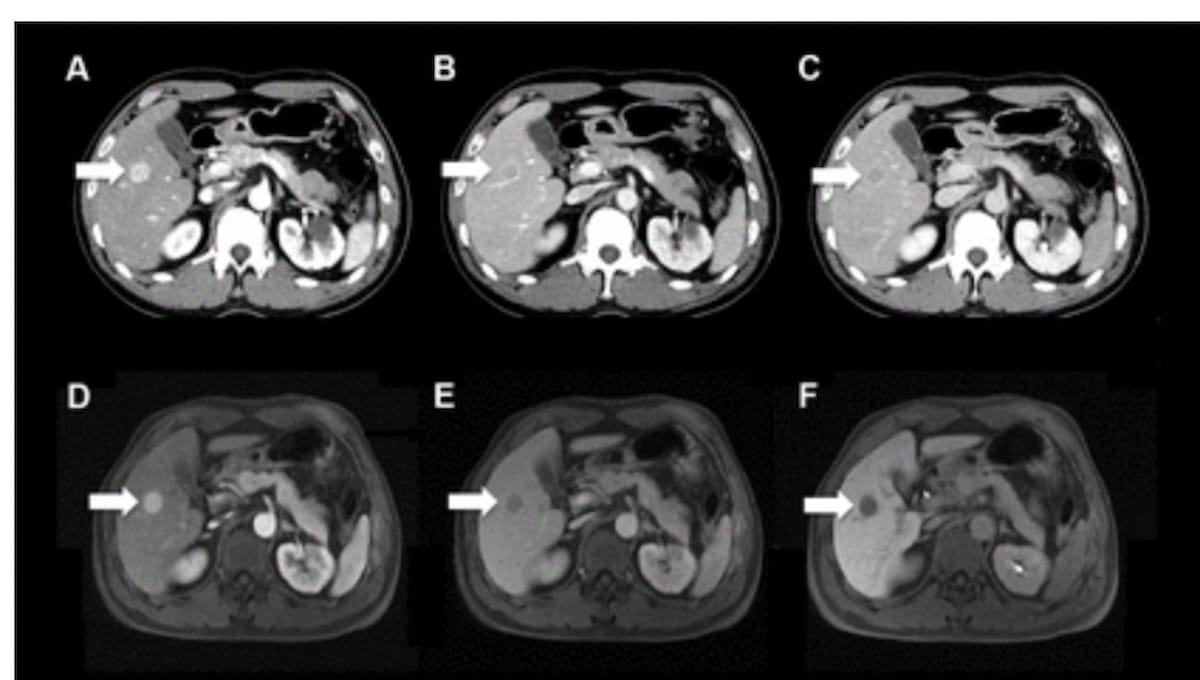

Are CT and MRI-Derived LI-RADS Assessments Effective for Detecting HCC in Cases of Non-Cirrhotic Chronic Hepatitis C?

Emerging research suggests that Liver Imaging Reporting and Data System (LI-RADS) category 5 (LR-5) assessment of computed tomography (CT) and magnetic resonance (MRI) scans has greater than 96 percent accuracy for detecting hepatocellular carcinoma (HCC) …